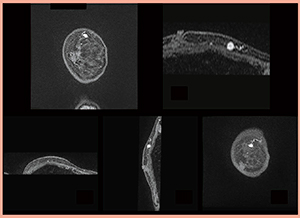

当院のRVS用MRIの撮像条件を表2に示す。呼吸停止時間は,1.5T,3T共に20秒である。RVSを行う際には,RVS用MRIの全シリーズ,全スライスを超音波診断装置に読み込むことができる。RVSでは4相のシリーズを切り替えて表示することが可能である。MPR画像を示す(図4)。

図4 RVS用MRIのMPR画像 |